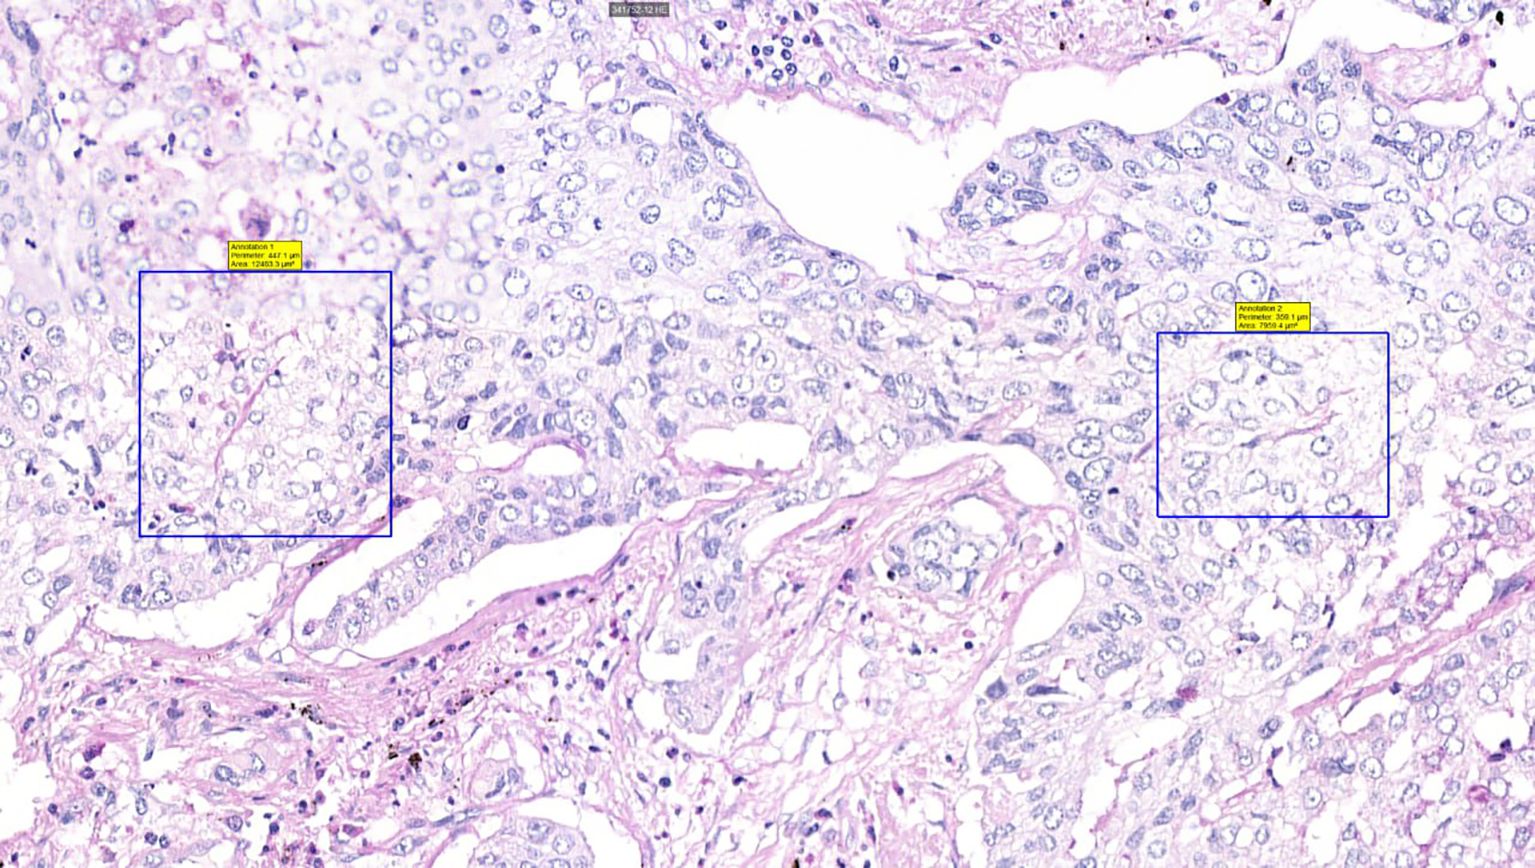

Surgically resected samples of NSCLC, formalin-fixed and paraffin-embedded, were stained with PAS to visualize VM. Figures 2, 3 were captured using the Pannoramic Confocal microscope (3D Histech) at 40x magnification. Figure 4 depicts blood vessels in NSCLC tissue, identified via IHC for CD31 at 400x magnification. Brown chromogenic staining highlights the vascular endothelium.

Figure 2. Histological sample of NSCLC with VM: tubular type, PAS staining, 40x magnification. A square indicates PAS-positive tubular VM structures, demonstrating characteristic PAS reactivity in vasculogenic mimicry patterns.

Figure 3. Histological sample of NSCLC with VM: patterned matrix type, PAS staining, 40x magnification. Squares highlight PAS-positive extracellular matrix sheets consistent with patterned matrix-type VM, demonstrating distinctive PAS reactivity in matrix-rich VM architectures.

The detection of VM poses a challenge. Broadly, VM can be classified into two types: tubular type (Figures 2, 5) and patterned matrix type (Figures 3, 6). In contrast, Figure 4 demonstrates CD31-positive endothelial-lined blood vessels in NSCLC, representing traditional angiogenesis-dependent vasculature.